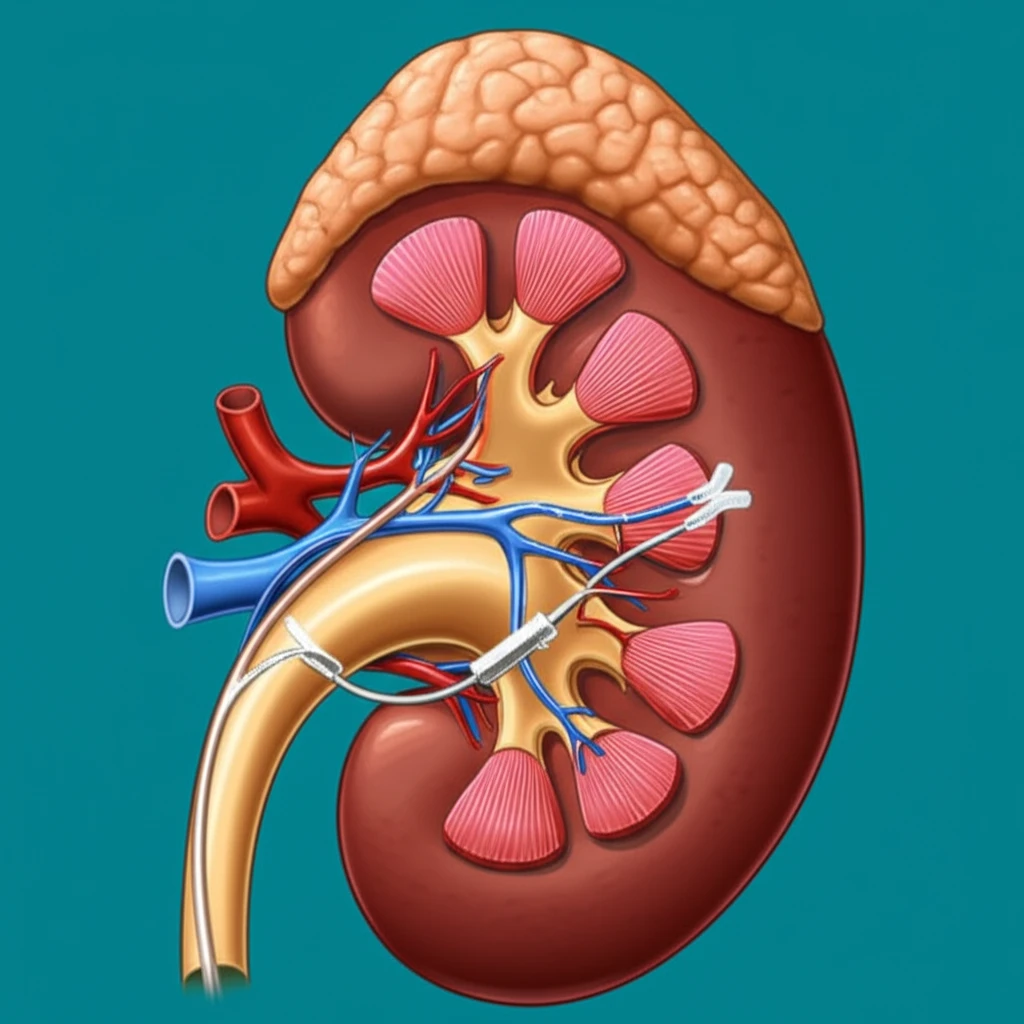

When it comes to pediatric urology, the health and well-being of our youngest patients are always the top priority. One common procedure, pyeloplasty, addresses a condition known as ureteropelvic junction (UPJ) obstruction, where the connection between the kidney and ureter is blocked. A critical aspect of this surgery involves drainage, and two primary methods have emerged: Double-J (DJ) internal stents and externalized uretero-pyelostomy (EUP) stents. This article dives deep into the comparative analysis of these two approaches, offering a comprehensive overview for parents and medical professionals alike.

The choice between DJ and EUP stents involves understanding the advantages and disadvantages of each. DJ stents, placed internally, have been a long-standing method, while EUP stents, which drain externally, offer a different set of considerations. This article aims to provide clarity on both, helping you grasp the essentials of each technique and their impacts on pediatric patients.

Both DJ and EUP stents play a crucial role in the success of pyeloplasty. DJ stents, placed internally, help keep the ureter open while the surgical site heals. They are typically removed in a second procedure. EUP stents, on the other hand, drain urine externally, offering an alternative method with its own set of considerations. Let's delve into a detailed comparison.